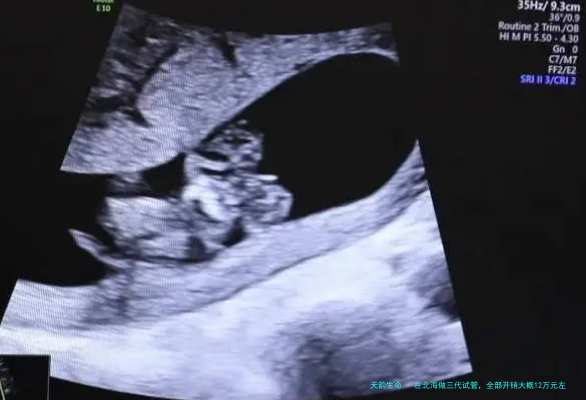

跟着现代诊疗技术的连续发展,人类辅助生殖技术为许多有生育困扰的家庭带来了期望,其中三代试管因能有效排查胚胎异常、提高受孕成功率,成为很多家庭的抉择。对于计划在北海发展三代试管的家庭来说,费用问题一直是注意的关键。结合北海当地的医疗收费水平和三代试管的技术流程,其全部开支大概在 12 万元左右,这笔费用涵盖了从术前准备到手术之后跟踪随访的多个关键环节,每一笔支出都与治疗的靠谱性和有效性紧密相关。